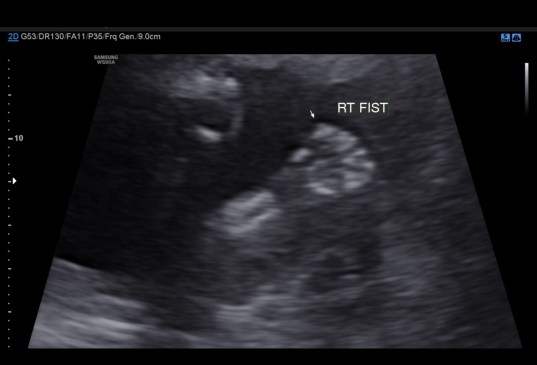

I seriously do not know where time is going, but it seems that after Kenley died the end of the year zooms by. Once Landon starts school again, everything just goes super fast. So yesterday was my anatomy scan. I was 18+5, and everything looked great. She was being stubborn though so we have to go back on November 16th for another ultrasound (obviously not complaining). We got to see her little face for a few seconds; the look like skeletons right now, but it was still cute. She also proved to us that she was indeed a female. She showed us her hands and feet, and also her cute little belly.